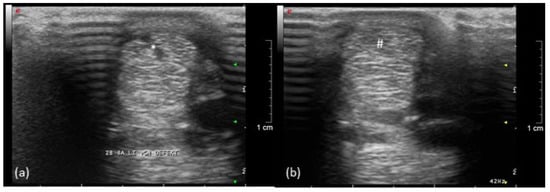

Figure 4.

Ultrasonographic image of the left forelimb of a pony, left is lateral: (a) acute (*) and (b) healing (#) tendon lesion of the SDFT (9 weeks after injection of collagenase).

A mild swelling occurred for several weeks in the bone marker regions with no other signs of inflammation or pain during palpation. During the lameness examination, in the 14th week, the implantation sites were no longer circumferentially enlarged. After walking and trotting on the treadmill during the first FluoKin measurement (“FluoKin 1”), a diffuse swelling of the lateral aspect of the metacarpal region appeared for three days. Two weeks after injection of collagenase, the pony showed a lameness score of 2 out of 5 in the left forelimb during walk and trot but maintained an even weight distribution while standing. The corresponding ultrasound examination of the left forelimb SDFT showed an acute, hypoechogenic tendon lesion in the center of the mid-metacarpal region with a slightly enlarged diameter (Figure 4). In the right forelimb, no signs of tendonitis were seen in the ultrasound in the 7th week. Five weeks after injection of collagenase, no lameness but a slightly more careful use of the left forelimb was observed during walk. There was a lameness score of 1 out of 5 during trot. Nine weeks after injection of collagenase, no gait abnormalities during walk and a barely noticeable lameness score of 1 out of 5 during trot were detected. Within the corresponding ultrasound examination in week 14, hyperechogenic lines in the tension direction were demonstrated in the remaining hypoechogenic lesion (Figure 4). Fifteen and thirty-three weeks after injecting collagenase, no lameness could be observed. The final ultrasound examination in the 37th week showed normal tendon tissue. The beads did not slip out of the tendon over the course of the study. The proper location of all beads in the tendon tissue was verified both with CT in week 7 and repetitive ultrasound examinations (4th week, 7th week, 14th week, and 37th week).